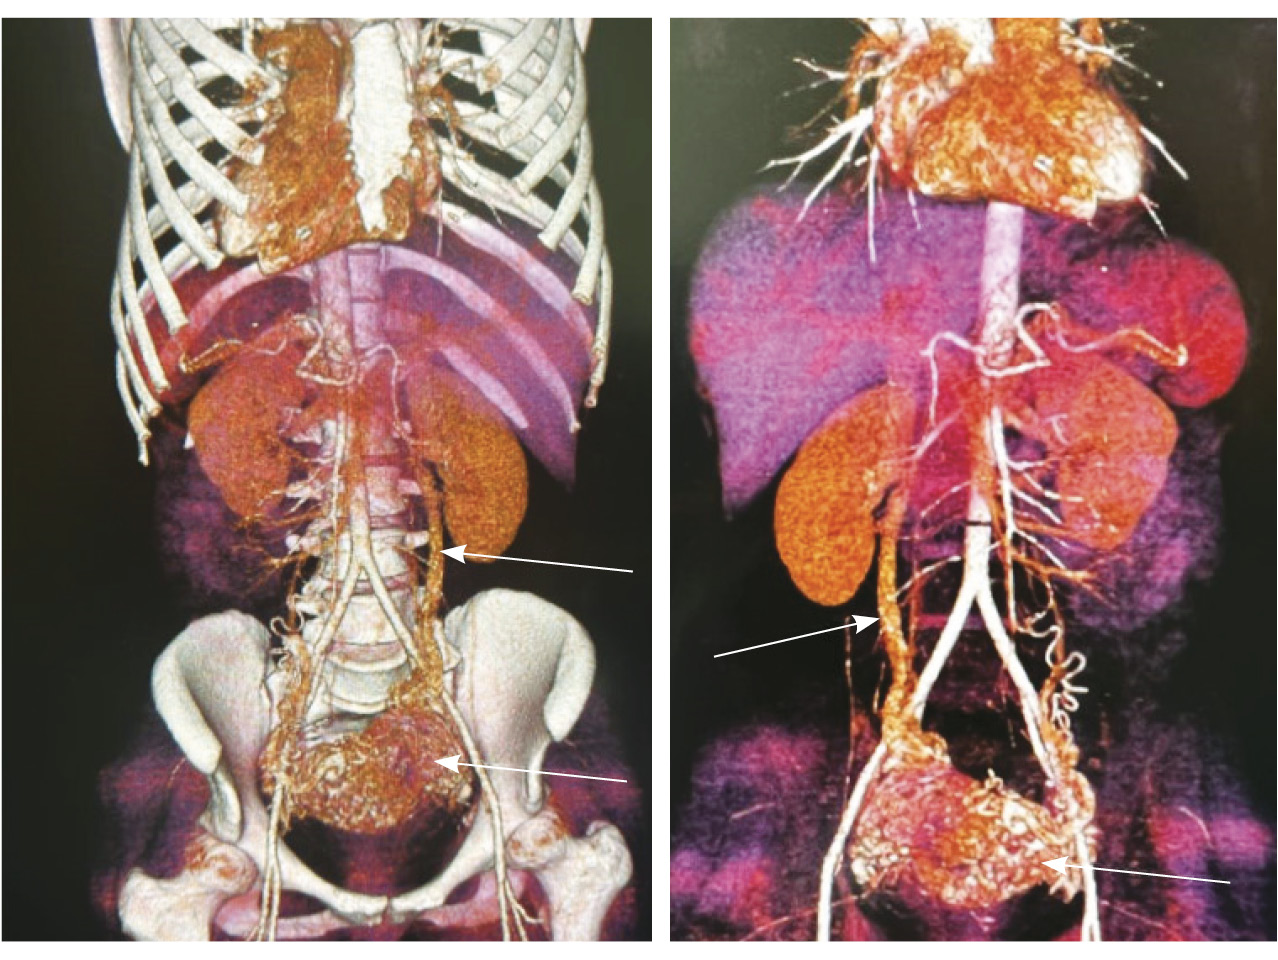

Исходя из клинической и визуальной картины, пациентке выполнено оперативное лечение. Первым этапом проведена эмболизация маточных артерий. Под местной анестезией раствором ропивакаина пунктирована правая лучевая артерия. Установлен интродьюсер 5F. Катетером НН последовательно катетеризированы левая и правая внутренние подвздошные артерии, выполнена ангиография. На ангиограммах: артериовенозная мальформация в проекции матки; афферентные артерии – маточные и цервиковагинальные – с обеих сторон, две ветви 1 мм в диаметре от левой внутренней подвздошной артерии; эфферентные сосуды – вены параметрия, внутренние подвздошные вены и яичниковые вены с обеих сторон (рис. 4).

Рис. 4. Данные рентгеноконтрастной ангиографии. А, Б – ангиограммы бассейнов правой и левой маточных артерий. Зоны патологической васкуляризации в проекции тела матки: массивная сеть измененных артерий и вен, ранний артериовенозный сброс в вены параметрия, внутренние подвздошные вены и яичниковые вены с обеих сторон. В, Г – ангиограммы бассейнов правой и левой цервиковагинальных артерий. Контрастирование зоны патологической васкуляризации в проекции шейки и нижнего отдела тела матки, ранний артериовенозный сброс в вены параметрия преимущественно слева и в левую внутреннюю подвздошную вену (стрелки)

Выполнена эмболизация маточных и цервиковагинальных артерий с обеих сторон материалом PVA (1000 мкм) и эмболами из гемостатической губки. На контрольных ангиограммах патологическое сосудистое сплетение не контрастируется, артериовенозный сброс устранен (рис. 5). Катетеры и интродьюсер удалены, выполнен компрессионный гемостаз, наложена асептическая давящая повязка. Контрастный препарат йодиксанол (320 мг йода/мл) – 300 мл. Эффективная доза – 1,8 мЗв.

Рис. 5. Контрольные снимки после эмболизации маточных и цервиковагинальных артерий. Ангиограммы бассейнов правой и левой внутренних подвздошных артерий. Правая маточная и цервиковагинальная артерии, а также патологическое сосудистое сплетение в их бассейне не контрастируются, ранний артериовенозный сброс устранен. Незначительное контрастирование сегмента патологической сети по единичной мелкой ветви внутренней подвздошной артерии справа, по двум мелким ветвям внутренней подвздошной артерии слева (указано стрелками)